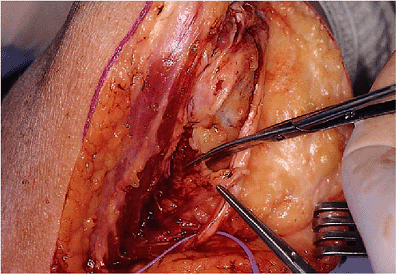

![]() |

|

Figure 18-18. The anterior capsule and brachialis muscle insertion are released from the anterior humeral cortex with a curved osteotome.